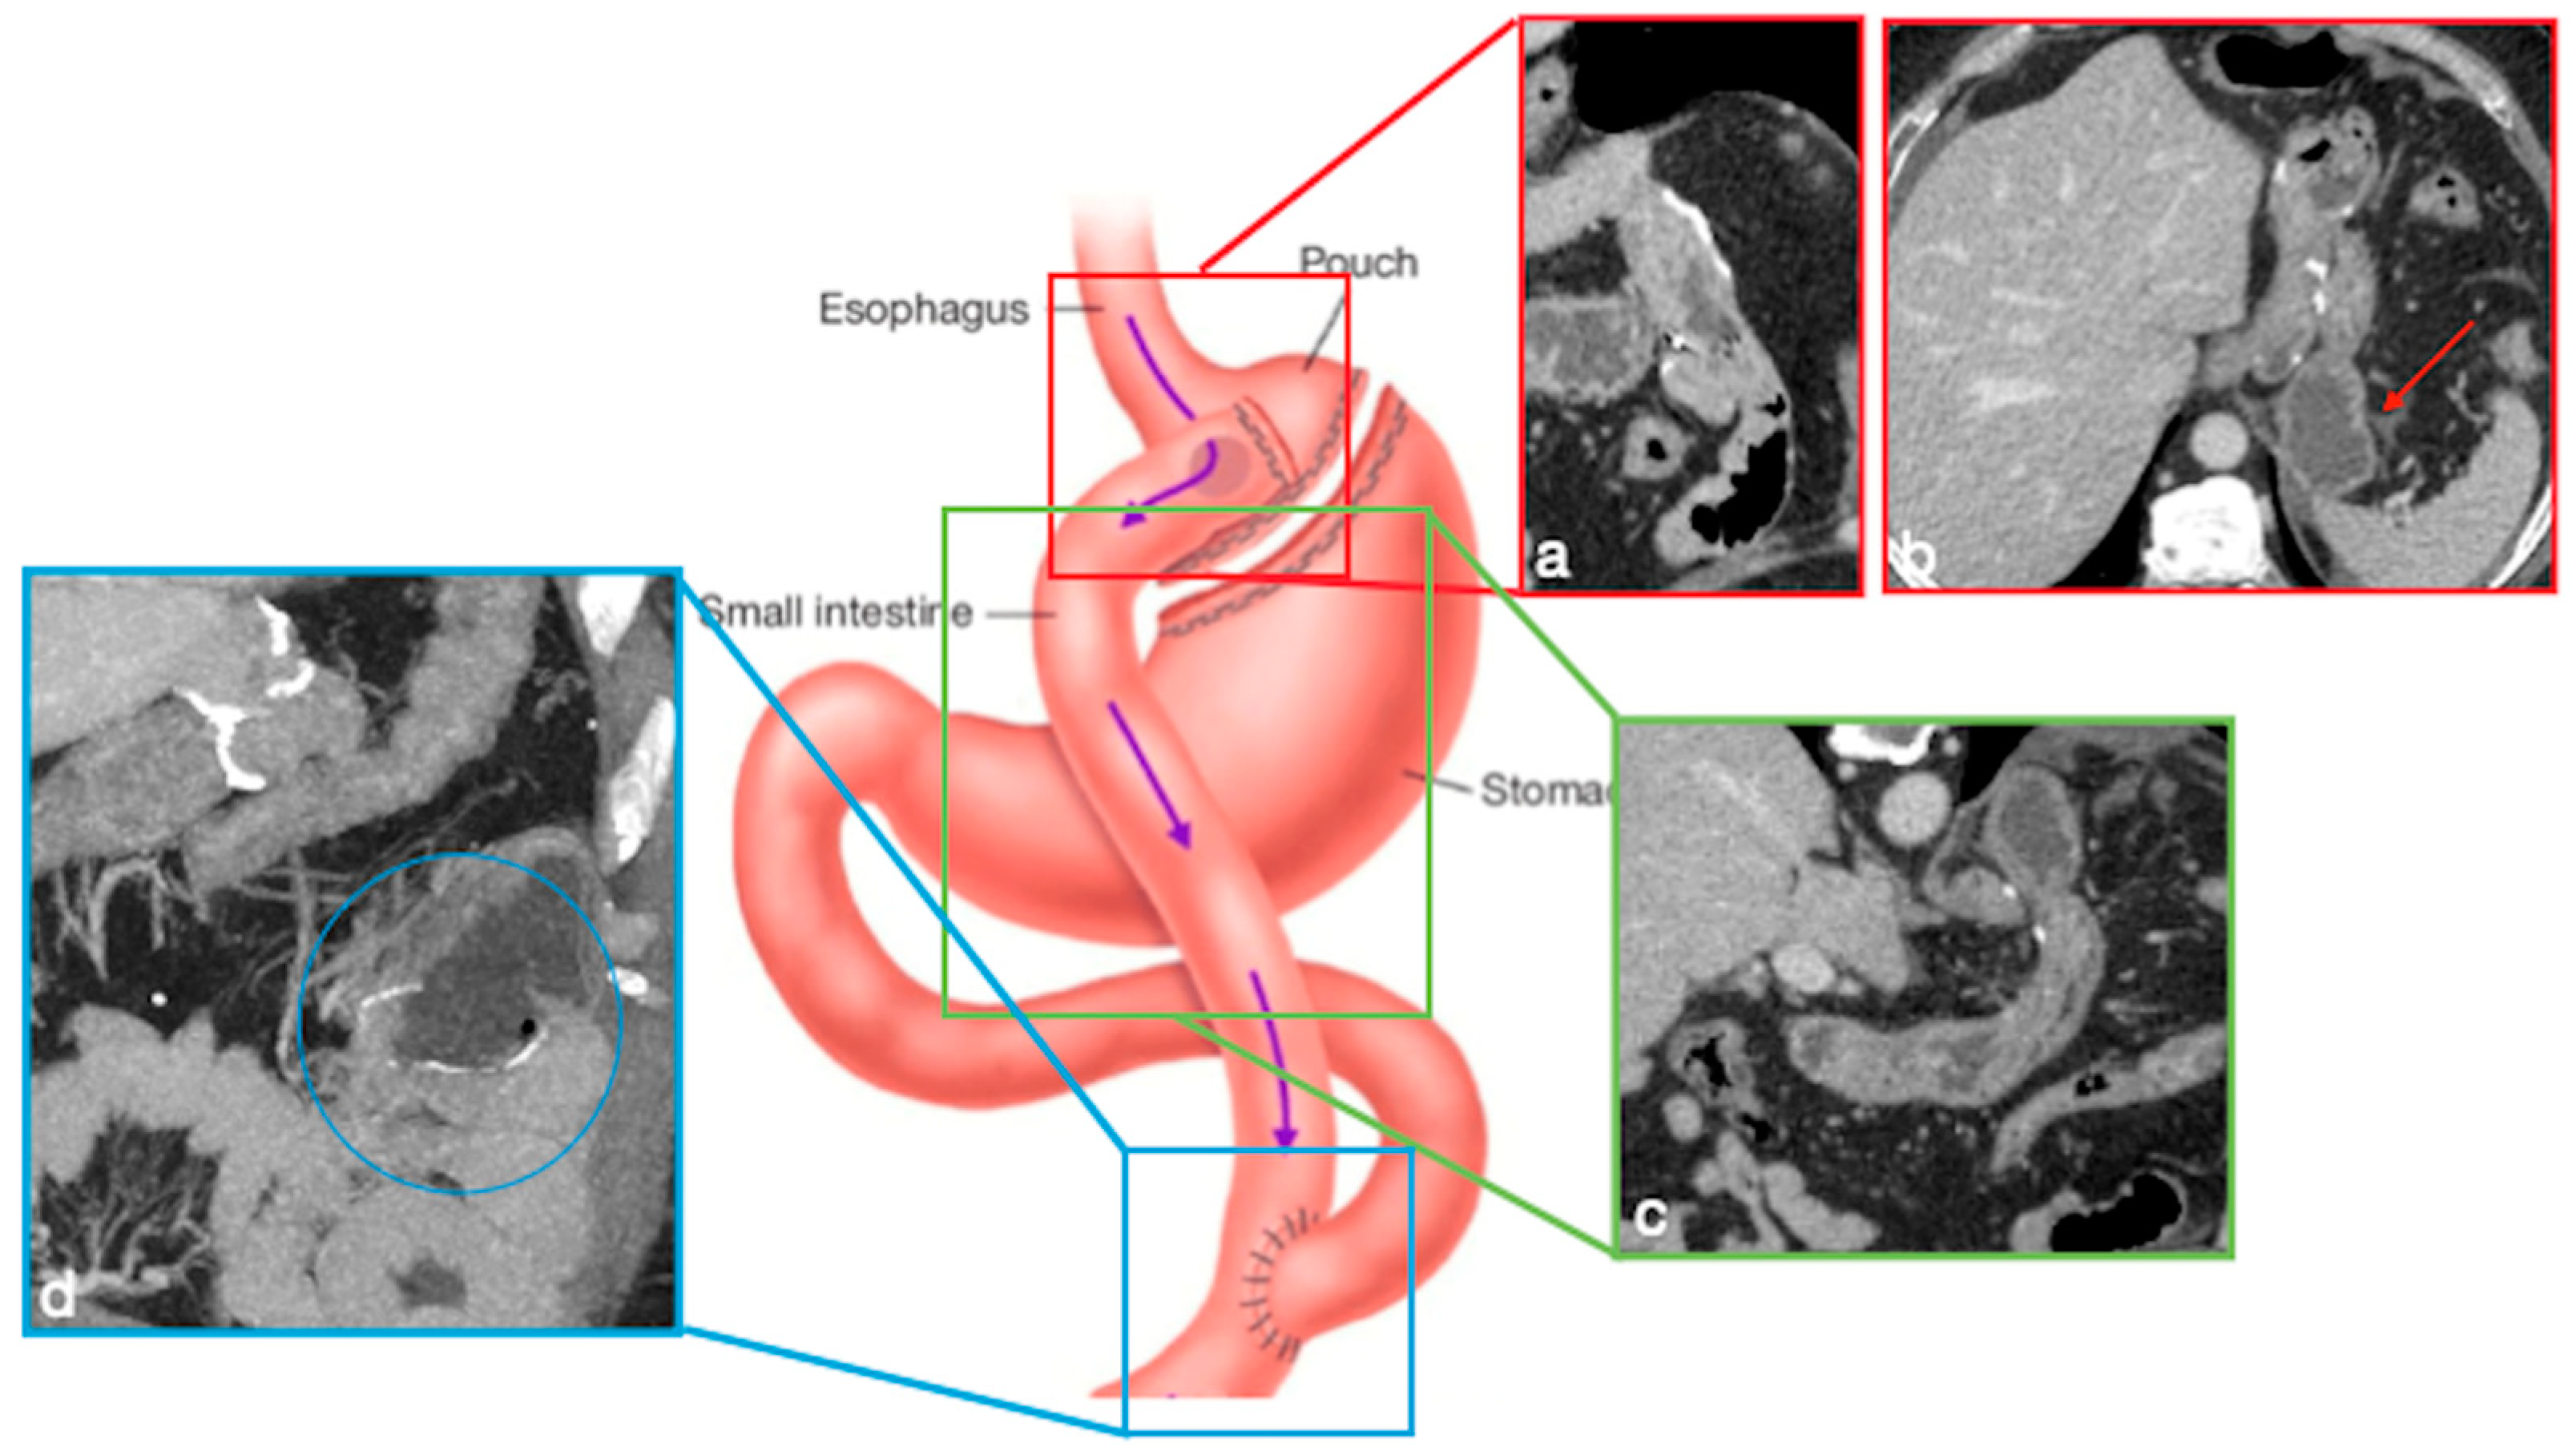

3.3.4. RYGB

- Stenosis

- Leak

- Small bowel obstruction

- Fistula

- Internal hernia

- Marginal ulcers

- Intussusception